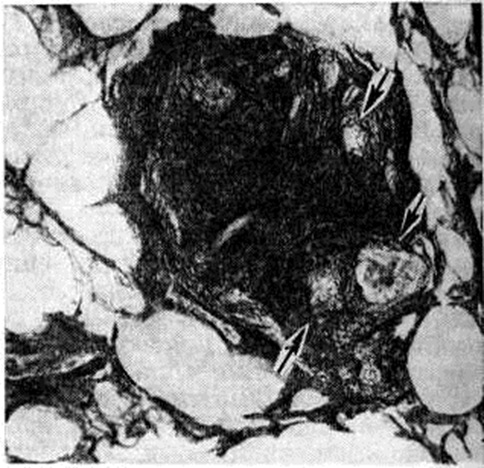

Туберкулёзные гранулемы имеют округлую форму, размеры их достигают величины зёрен проса (просовидные бугорки), но могут быть и несколько крупнее. В зависимости от реактивности организма гранулемы могут быть экссудативными, состоящими преимущественно из лимфоидных клеток, экссудативно-продуктивными, продуктивными и некротическими; последние встречаются при резком угнетении защитных сил организма. Типичные продуктивные туберкулёзные гранулемы состоят из эпителиоидных клеток и гигантских клеток Пирогова — Лангханса, а также расположенных по периферии лимфоидных клеток. Иногда в центре гранулемы формируется участок казеозного некроза. При импрегнации серебром (смотри полный свод знаний: Серебрения методы) в гранулеме вне гигантских клеток выявляются аргирофильные волокна (рисунок 3). Гранулемы могут сливаться, образуя очаги, в которых различаются элементы стромы отдельных составляющих их гранулем. При заживлении клеточные элементы частично рассасываются и на месте гранулемы развивается небольшой рубчик неправильной паукообразной формы.